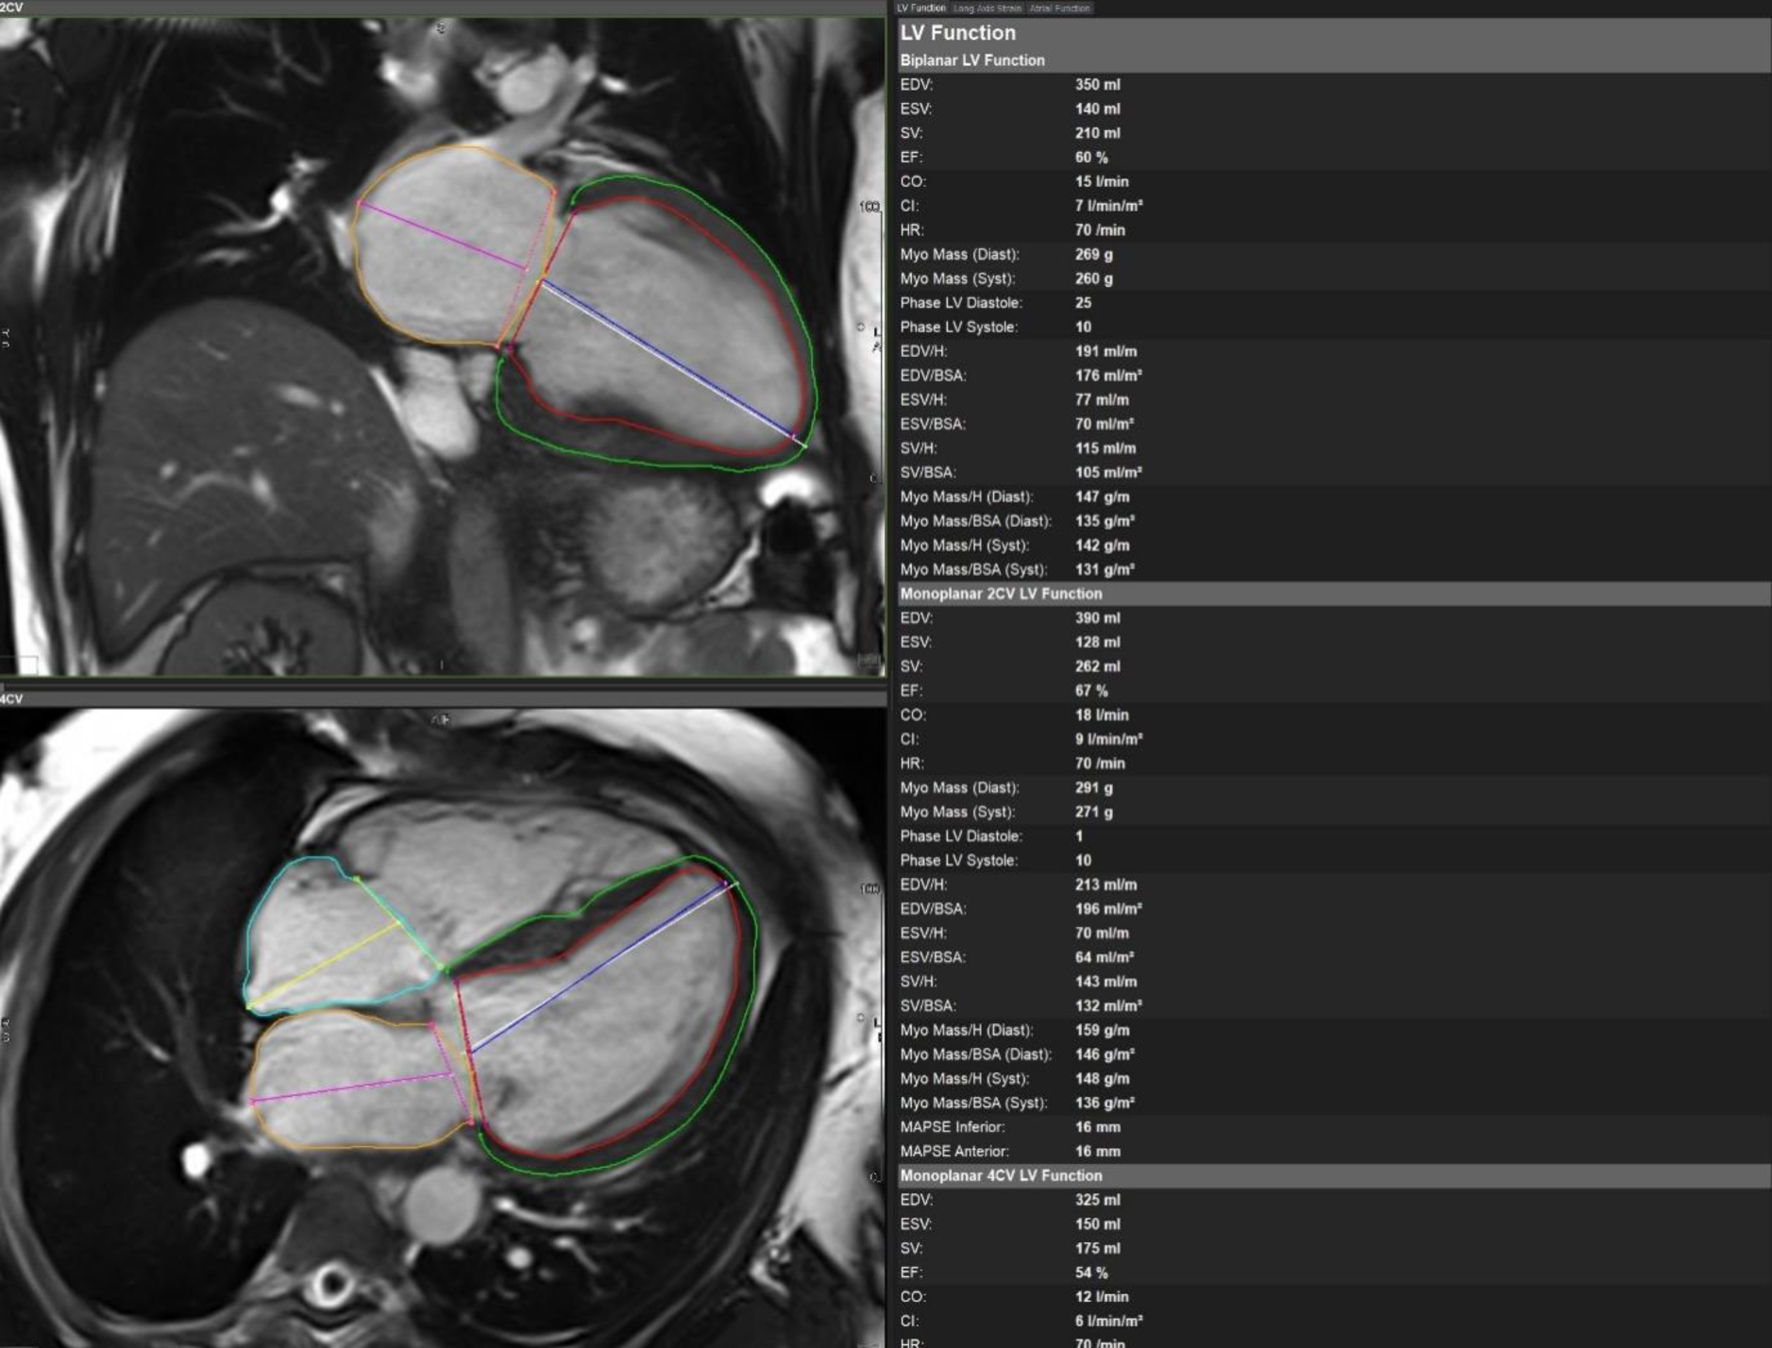

Initial bedside echocardiogram, done while intubated in ICU, showed LVEF of 30-35%, dilated LV at 6 cm, and a central jet of AR deemed moderate. Departmental TEE corroborated the impression of moderate AR. Quantitative assessment was, however, limited by eccentric AR jet (Fig. 1). Coronary angiogram showed no obstructive coronary artery disease. Two weeks later, CMRI showed a severely dilated LV with indexed end diastolic volume of 176 mL/m2 (Fig. 2). There was moderate eccentric LV hypertrophy, but preserved LVEF at 56% and stroke volume of 197 mL. Aortic valve images demonstrated a trileaflet aortic valve with partial fusion of the left and right coronary cusps, and severe AR due to failure of coaptation between these cusps (Fig. 3). Aortic regurgitant fraction was 45-50% by LV-RV stroke volume difference. Unfortunately, flow analysis was limited as the imaging plane was placed on the aortic valve rather than the sino-tubular junction, which would underestimate regurgitant fraction (Fig. 4). The AR was felt to be severe based on qualitative assessment, large, holodiastolic jet extending into LV, aortic diastolic flow-reversal, and regurgitant fraction > 45% plus LV dilatation. There was no systolic anterior motion or LVOT obstruction, and no late-gadolinium enhancement, suggesting no myocardial fibrosis, infiltration, or infarction. There was no fibrosis detected on T1 mapping. Discrepancy in LVEF between imaging modalities was explained by myocardial stunning post-arrest. AR severity was underestimated on echocardiography due to the eccentricity of the AR jet.

Figure 2. Cardiac magnetic resonance imaging with biplane left ventricular volumes and function.